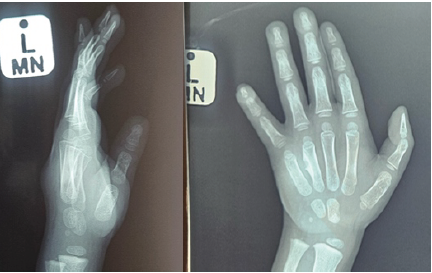

A radiograph of the hand showed periosteal reaction with a lytic lesion with well-defined borders over the ulna cortex of the metacarpal bone of the left ring finger (Fig. 2).

Figure 2: Left hand anteroposterior (AP) and lateral radiographs. Showing 4th metacarpal bony changes. AP X-ray shows the “crab claw” sign.